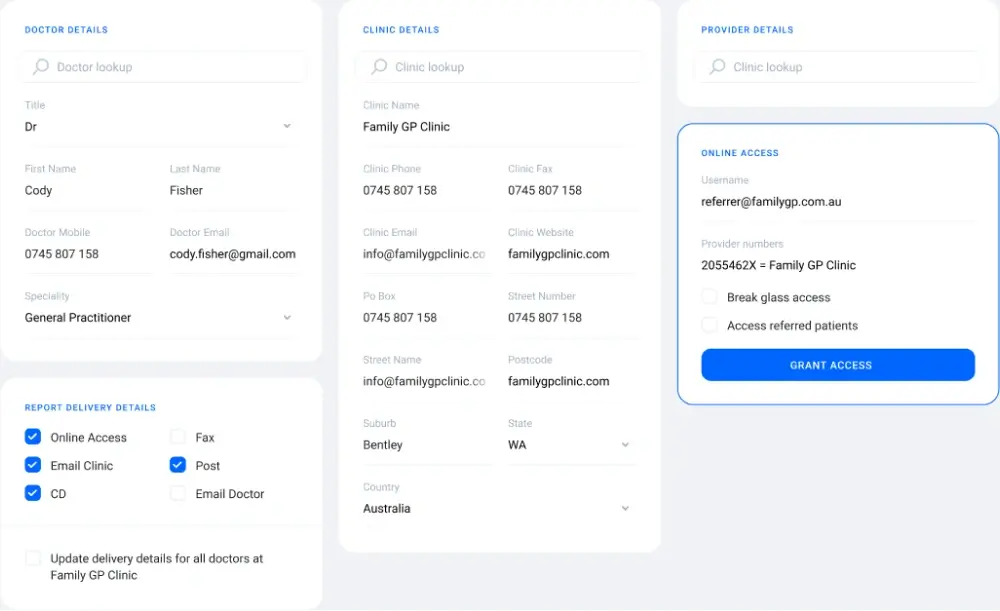

Access setup

Grant access with ease

Setting up access for referrers is straightforward. Navigate to the referrers module, select the desired referrer, and click 'Grant Access'. QUBS will automatically send an email to the referrer with their login credentials.

Setting up access for referrers is straightforward. Navigate to the referrers module, select the desired referrer, and click 'Grant Access'. QUBS will automatically send an email to the referrer with their login credentials.